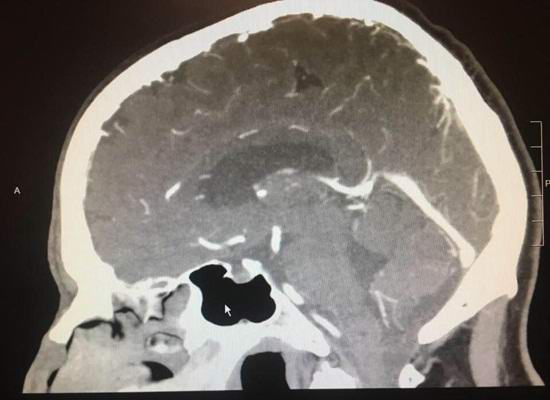

Paul Wood, žijící ve městě Lodai, si stěžoval na bolesti hlavy bolest před několika měsíci. Když se Američan otočil nemocnici, byl mu diagnostikován nádor na mozku. Přiřazeno riskantní operace se však den před tím náhle ukázalo, že nádor prostě zmizel. Doktoři nevěřili svým očím, když Rentgen ukázal, že mozek pacienta se vrátil do zdravého stavu stav.

Specialisté uznávají, že ve vzácných případech, maligní nádor může začít ustupovat sám až do úplné zmizení. Nicméně, pro jakýkoli materialistický úvahy, to se nemůže stát za jeden den.